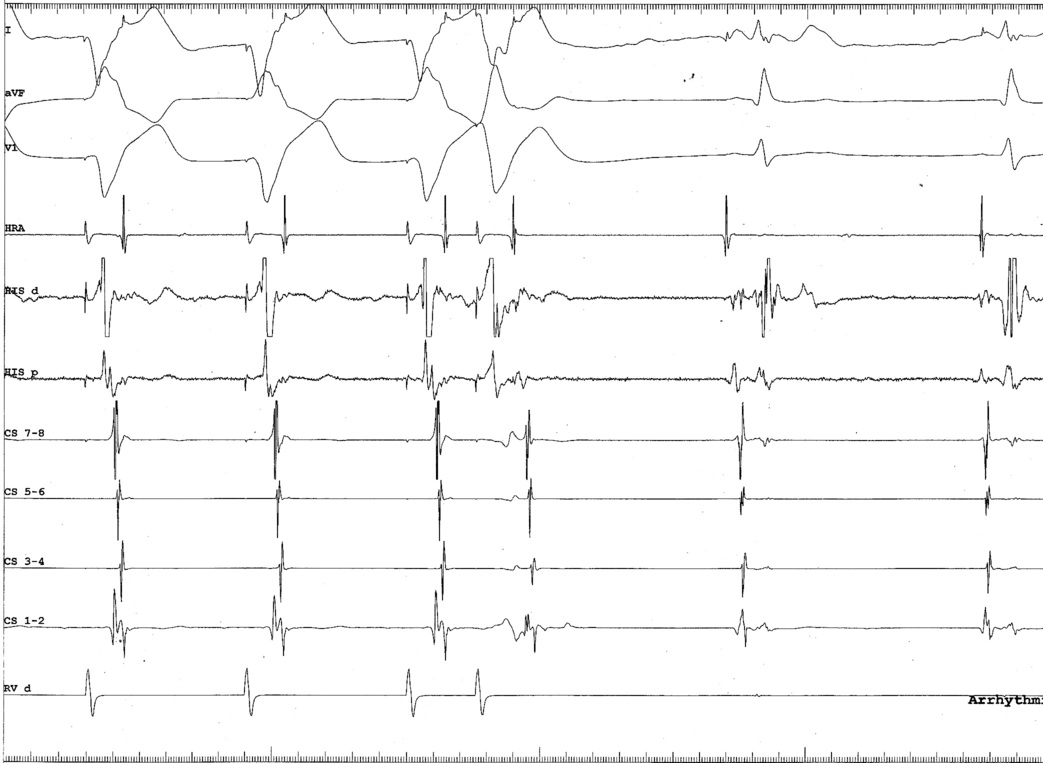

AP slant - Earliest A and earliest V may be distant

ap_med_lat1.jpg

ap_med_lat2.jpg

ap_med_lat3.jpg

AP slant - AP potential more important

pot_late_a.jpg